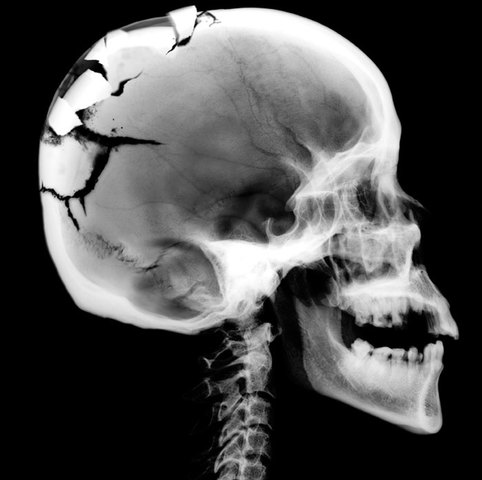

1) Mi mamá se cayó por las escaleras mientras me sostiene.

2) Mi cráneo se rompió.

3) Valamos a San Antonio caso dos semanas para ver a médico.